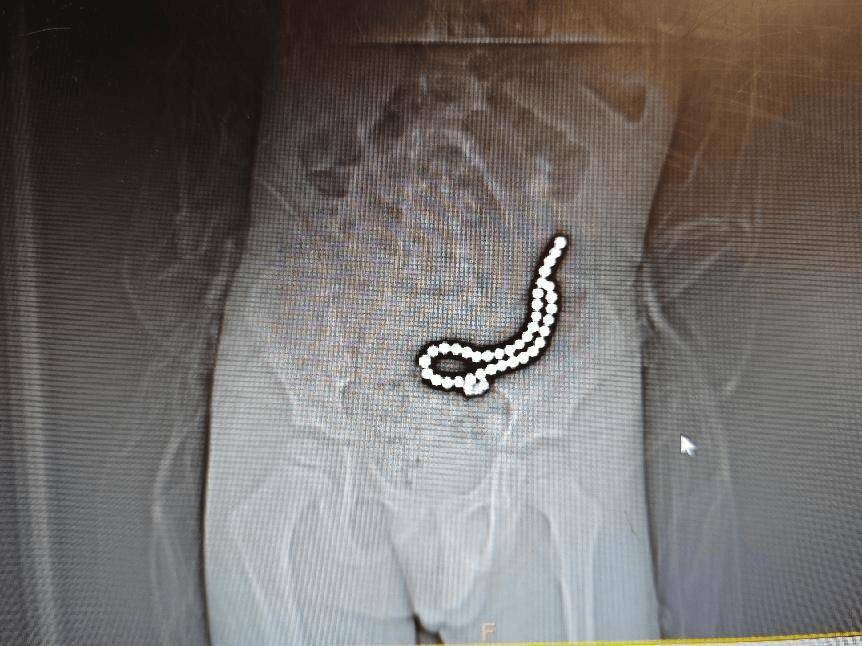

经过初步的影像学检查,医疗团队发现:病人体内竟然有37颗异物,连在一起呈手串状,并伴有小肠穿孔。

术前腹部DR片